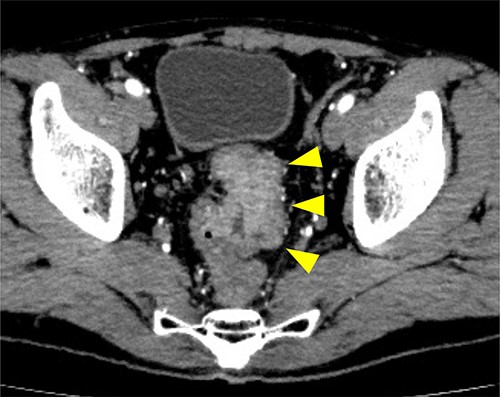

Subsequently, we performed transrectal drainage of the abscess in the lithotomy position without endoscopy. After the incision of the excluded rectal mucosa at 7 cm from the anal verge by the electric scalpel and penetration of the abscess wall by the Kelly clamp, a massive purulent discharge was observed. Next, a transanal rectal drainage tube (MIT drain®, effective length 12 cm; Create Medic Co., Ltd, Yokohama, Japan) was inserted into the abscess cavity without the use of a guide wire, and saline irrigation was performed. After transrectal drainage, the patient’s pain and inflammatory laboratory findings improved rapidly. Pelvic CT showed shrinkage of the cavity 3 days after the drainage (Fig. 3). Bacterial culture test and cytology of the drainage contents revealed negative growth and no malignancy, respectively. The biopsy results showed moderately differentiated tubular adenocarcinoma. The inserted tube was removed on the seventh day after the drainage, and the patient was discharged on the eighth day. In the outpatient department, total colonoscopy revealed that the exclusion from outside the rectal wall on the anal side of the tumor diminished, and the incised mucosa healed as a scar. Ink sticks were marked near the scar on behalf of the combined resection of the tumor. Pelvic CT revealed that the pelvic abscess had disappeared 1 month after drainage (Fig. 4).

Preoperative CT examination one month after drainage. Thickening of the rectal wall is demonstrated (arrowheads); however, the pelvic abscess completely disappeared.